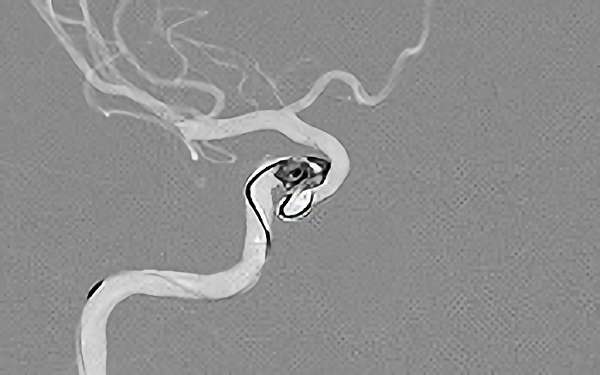

'26年4月

左後下小脳動脈瘤

80代

大阪府の病院

No.1631 手術前

No.1631 手術中

No.1631 手術後